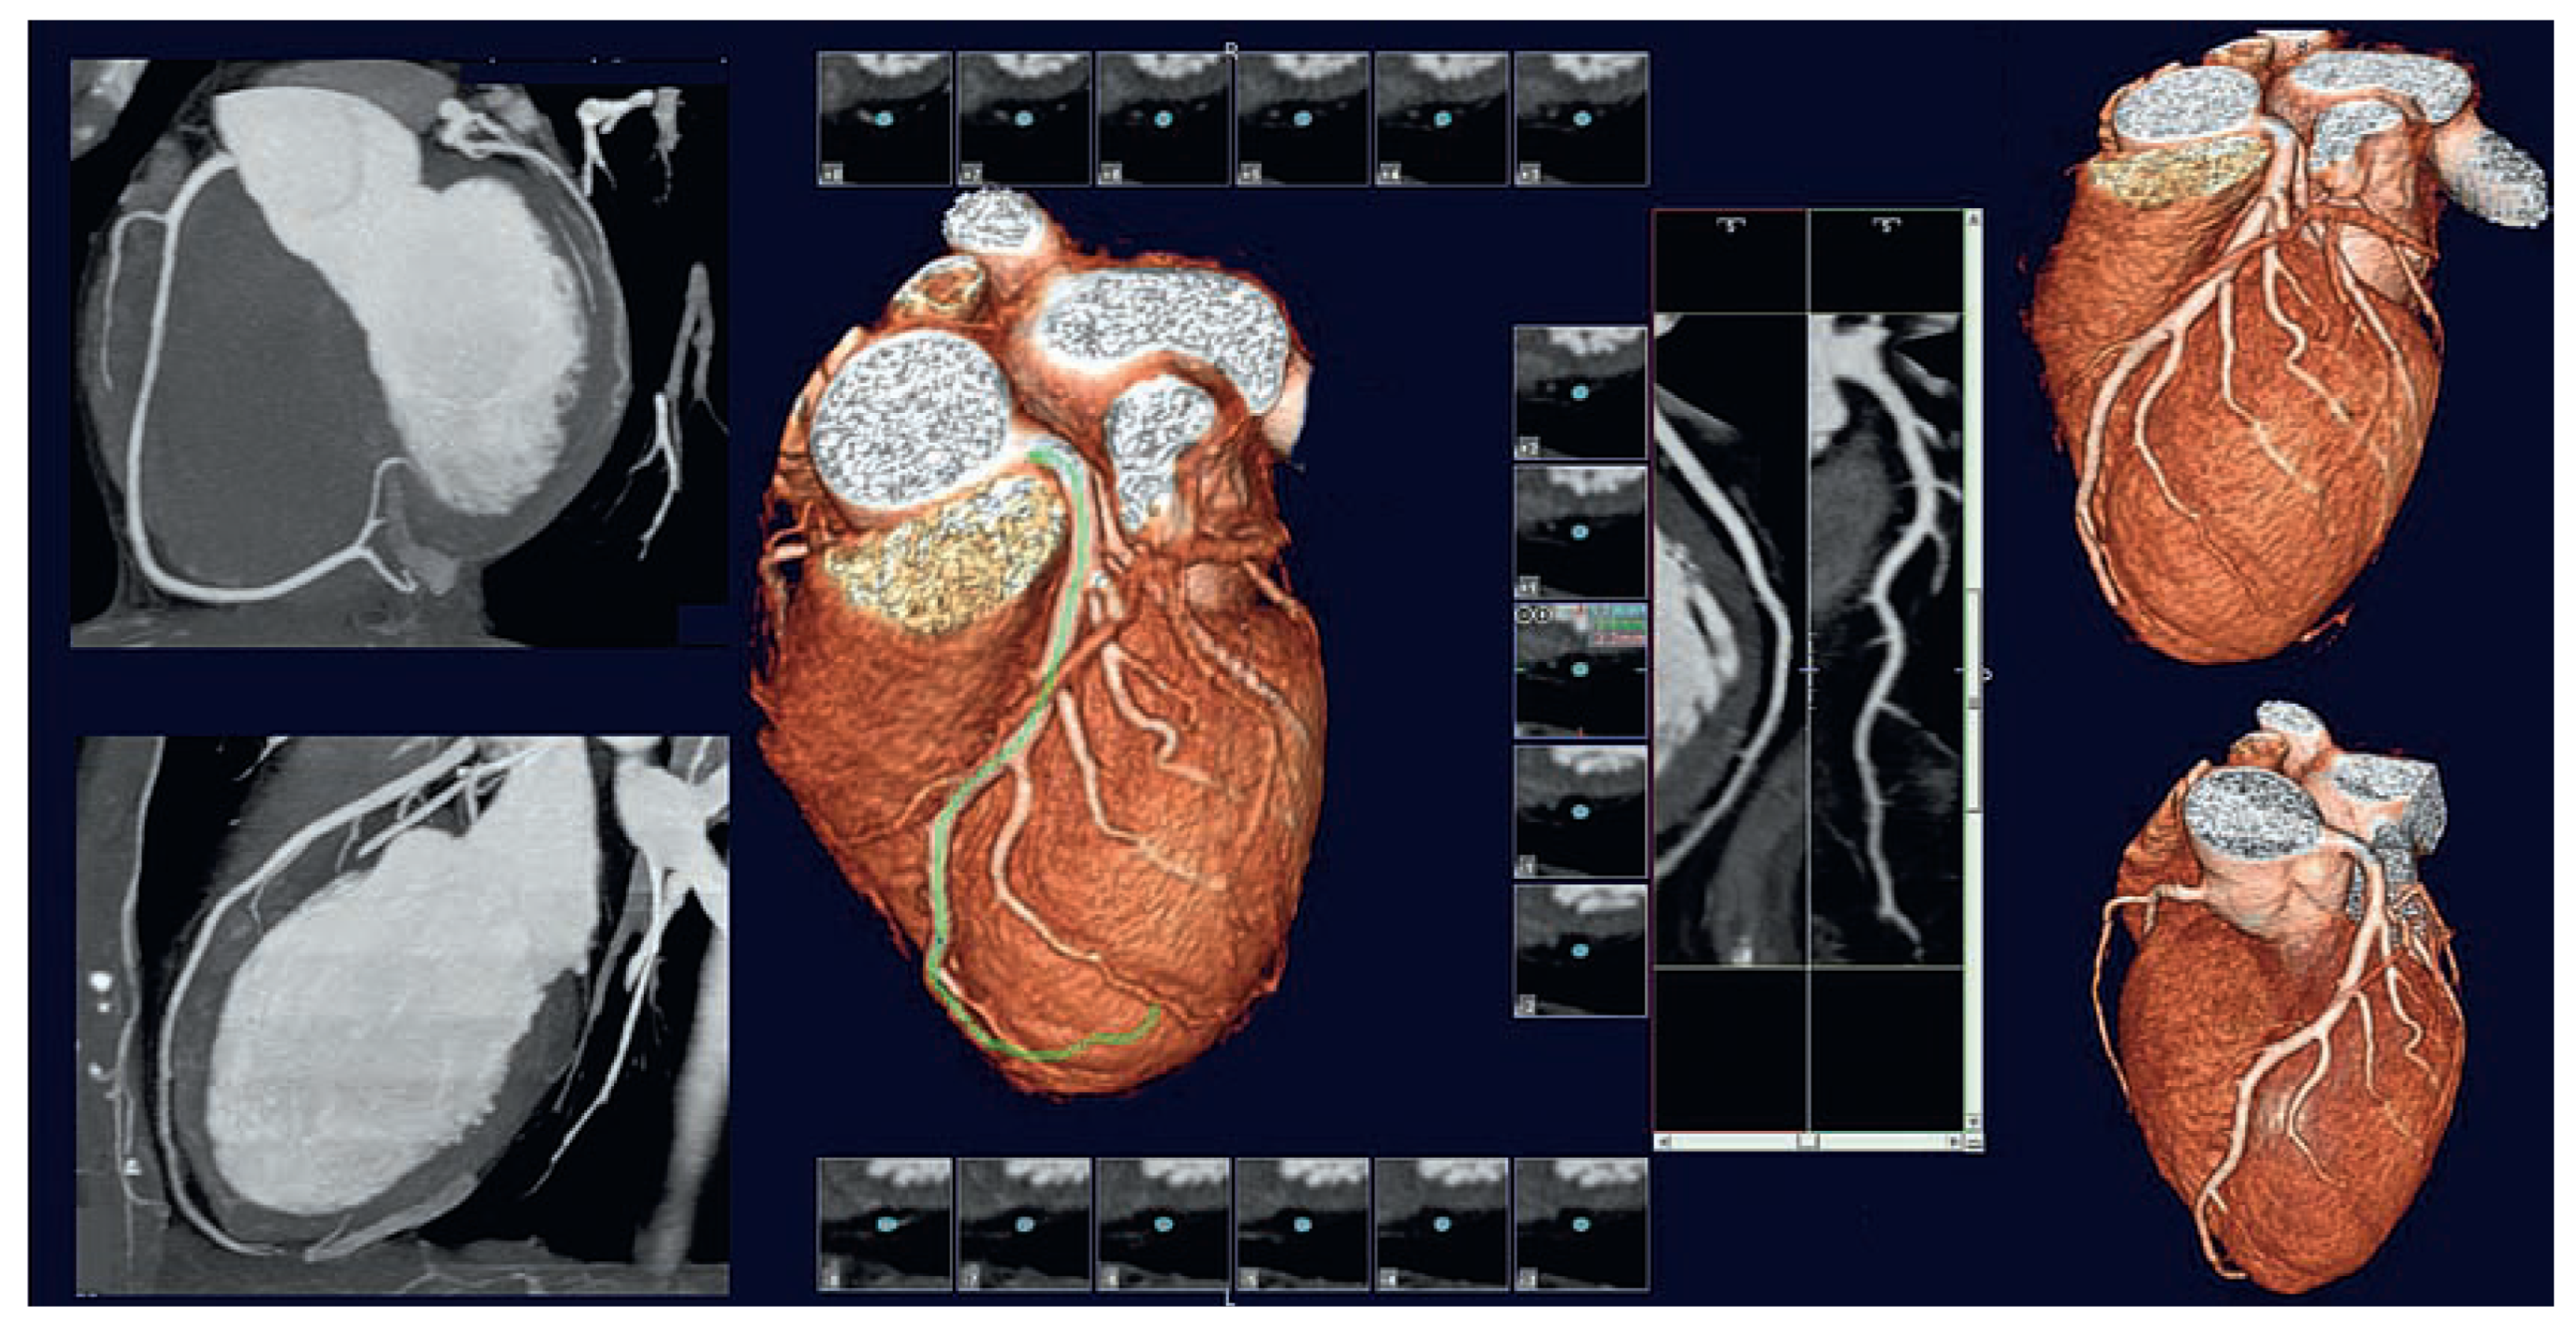

Coronary CTA is also highly recommended for follow-up evaluation of coronary bypass grafts. Unlike invasive coronary angiograms it does not require accurate localisation of ostia of venous grafts for selective contrast injections. CTA was shown to be accurate and reliable test for detection of bypass grafts stenosis as well as patency of surgical anastomosis with native coronary arteries. With appropriate imaging protocols, both arterial grafts from mammary arteries and venous grafts can be visualised and evaluated within a single acquisition with a single bolus of contrast agent. With volume rendering of the 3D data acquired by CTA, the topology and localisation of grafts is more accurate than traditional 2D coronary angiograms. Also, the same data acquired for evaluating the bypass grafts allow simultaneous evaluation of the native coronary arteries and assessment of their segmental lesions proximal or distal to the site of graft anastomosis.

With the ability to clearly identify vascular calcifications, coronary CTA provides additional valuable information on plaque characterisation. Detection and quantification of coronary calcium score have been well established as reliable criteria for evaluating risk factors of coronary artery disease. The latest generations of CT scanners also provide images that allow differentiating between different types of vascular plaques based on their tissue density ranging from lipid to fibrous to calcified plaques. While extreme calcifications of the coronary arteries may alter the accuracy of quantitative analysis of the degree of vascular stenosis it remains indicative of the severity of coronary disease.